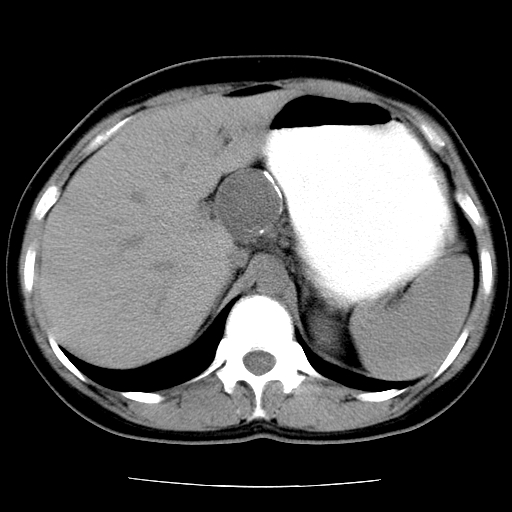

标题: CT16892:女40Y,急性阑尾住院!

女40y,急性阑尾住院!术前发现请会诊!

考虑门静脉瘤样扩张可能,建议增强扫描

胰头假性囊肿也有可能,建议增强

病灶位于门静脉的位置 ,有层面显示血管夹层样改变 ,考虑是门静脉瘤样病变1

病灶位于门静脉的位置 ,有层面显示血管夹层样改变 ,考虑是门静脉瘤样病变,建议进一步增强ct检查。

肝门区囊性占位,壁有钙化,考虑良性。来源难定。